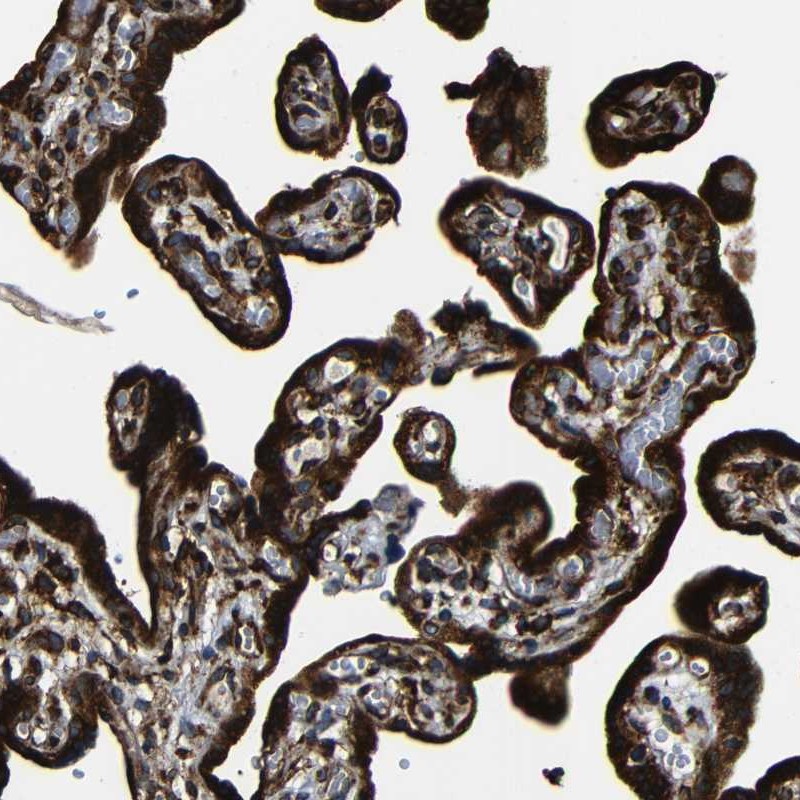

Immunohistochemistry analysis in human placenta and skeletal muscle tissues using Anti-RRBP1 antibody. Corresponding RRBP1 RNA-seq data are presented for the same tissues.